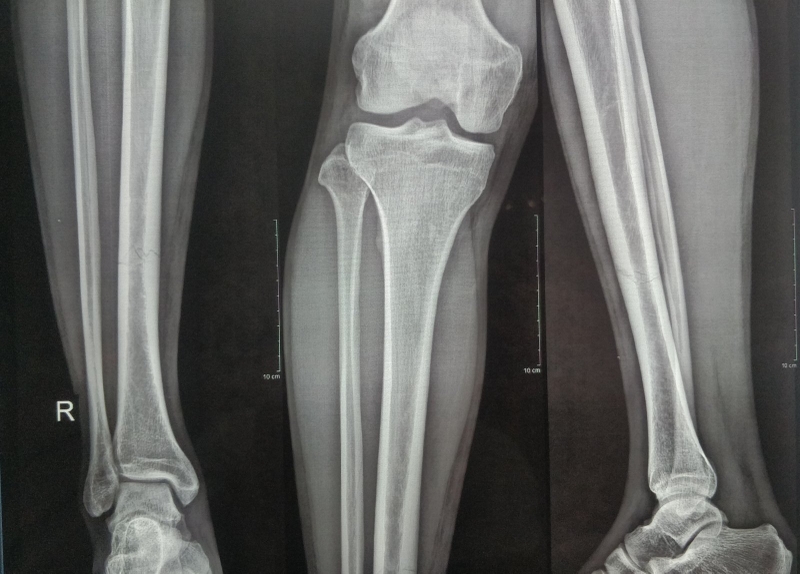

Rạn xương chày là một trạng thái trong đó xảy ra vết nứt nhỏ hoặc bè xương chày mất liên tục, nhưng xương không bị chia rời hoàn toàn. Các điểm quan trọng của rạn xương bao gồm đặc điểm về vết nứt nhỏ trên vỏ xương, khác biệt với gãy xương thông thường.

Lưu ý rằng mỗi trường hợp rạn xương chày có thể đòi hỏi một phương pháp điều trị riêng biệt. Bác sĩ có thể yêu cầu các xét nghiệm hình ảnh như chụp X-quang để đánh giá mức độ tổn thương và đề xuất phương pháp điều trị phù hợp. Đối với những trường hợp nghiêm trọng, có thể cần thiết phẫu thuật và quản lý chăm sóc từ các chuyên gia y tế.